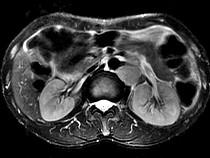

问题 男,54岁、1年前行胃癌切除术,现消瘦乏力、左锁骨上淋巴结肿大,影像检查如图,最可能的诊断是()

选项 A.淋巴瘤 B.腹膜后淋巴结转移 C.肾上腺腺瘤 D.肾上腺增生 E.腹膜后纤维肉瘤

答案 B